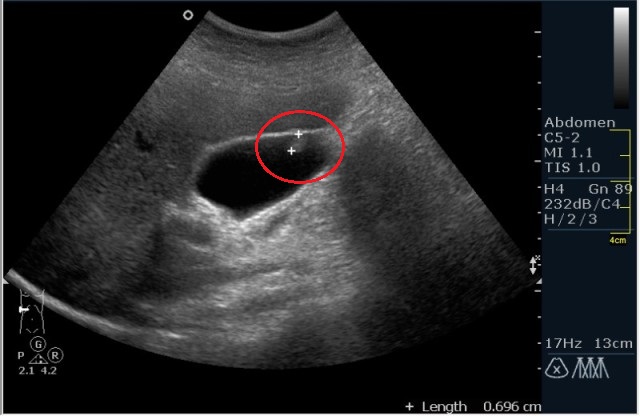

Основным методом диагностики этих новообразований является ультразвуковое исследование (УЗИ) брюшной полости.

На результатах этого исследования хорошо видны как образования на ножке, так и образования, расположенные непосредственно на слизистой оболочке пузыря. Если же результаты УЗИ не позволяют специалисту однозначно поставить этот диагноз, то применяется методика эндоскопической ультрасонографии, которая позволяет более точно определить строение полипа и его локализацию. Суть этой методики заключается во введении в кишечник ультразвукового датчика.